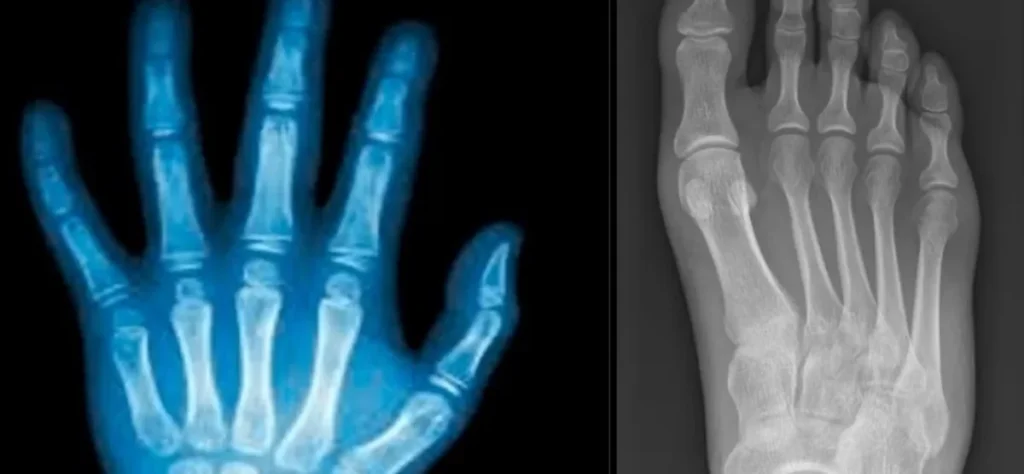

Cientistas desenvolvem cola que regenera ossos quebrados em apenas 3 minutos

Inovação chinesa promete revolucionar o tratamento de fraturas e reduzir o tempo de recuperação de pacientes